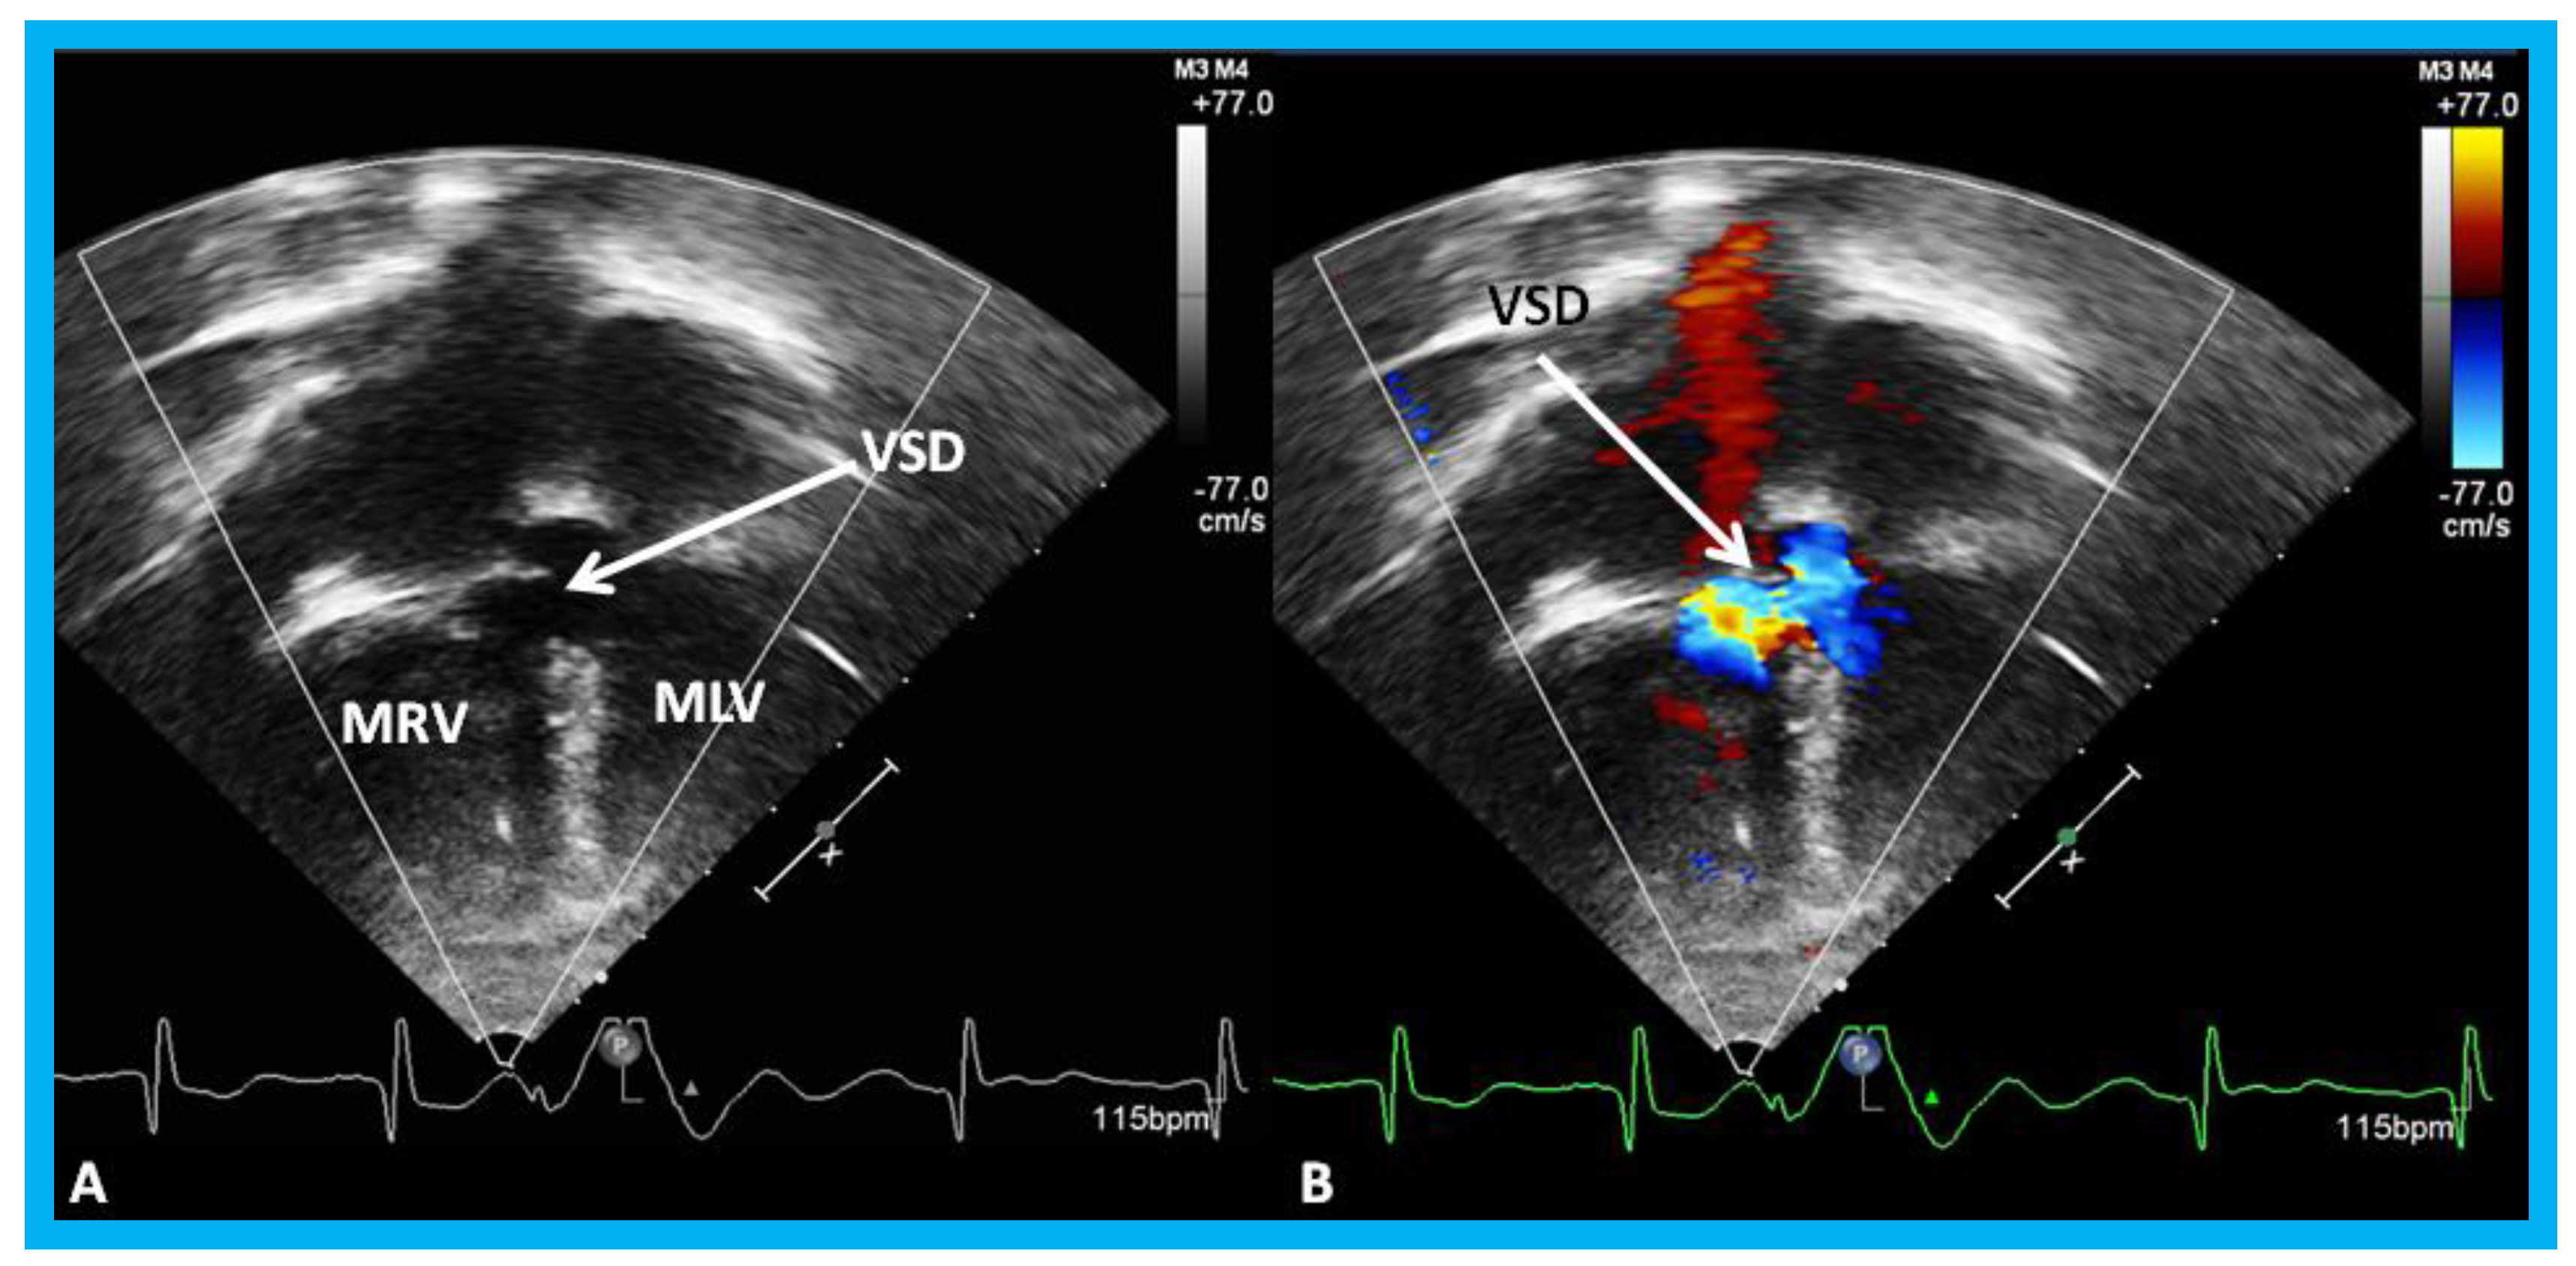

Figure 18. Selected video frames by two-dimensional (A) and with color flow imaging (B) from apical four-chamber view from the right chest demonstrating morphologic right (MRV) and morphologic left (MLV) ventricles and a large VSD (ventricular septal defect) in a patient with dextrocardia. Reproduced from Yarrabolu T.R., et al. [23].

Children 07 00034 g018

Congenitally corrected transposition of the great arteries (CCTGA) is a rare CHD. The anatomic, physiological, and clinical aspects of CCTGA with particular attention to sub-pulmonary obstruction of the morphologic LV caused by of the membranous ventricular septal aneurysm in patients with both levocardia and dextrocardia [22,23,24] were described in the past. The ventricular morphology and the sub-pulmonary aneurysm were illustrated angiographically elsewhere [22,23,24], and the echo-Doppler features of these anomalies will be demonstrated in Figure 17, Figure 18, Figure 19 and Figure 20.